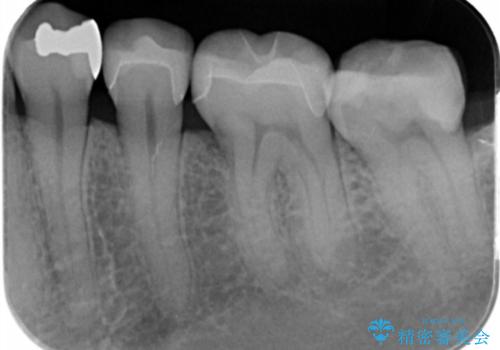

- 銀の詰め物が目立ので白くしたいとの事で来院。

とりあえず奥の二つから白くしたいとの事だったので

銀の詰め物を外し、e-maxインレーにしました。

e-maxインレーは銀の詰め物に比べ歯との隙間ができにくく

虫歯の再発リスクが少ないです。